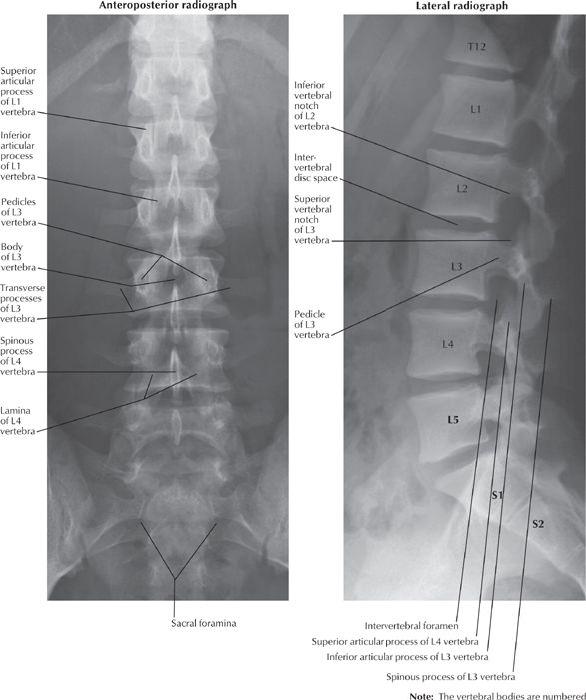

Медицинские снимки: рентген позвоночника сбоку